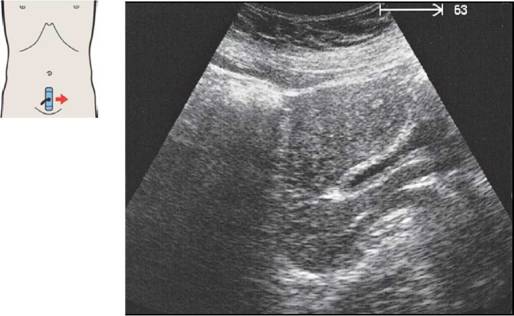

Печень при продольном сканировании

63 Левая печеночная вена, круглая связка, граница между медиальным и латеральным сегментами, хвостатая доля

Круглая связка (облитерированная пупочная вена) расположена между левой ветвью воротной вены и передним нижним краем печени.

Каудальная часть медиального сегмента квадратной доли расположена между круглой связкой и желчным пузырем. Квадратная доля является частью IV субсегмента.